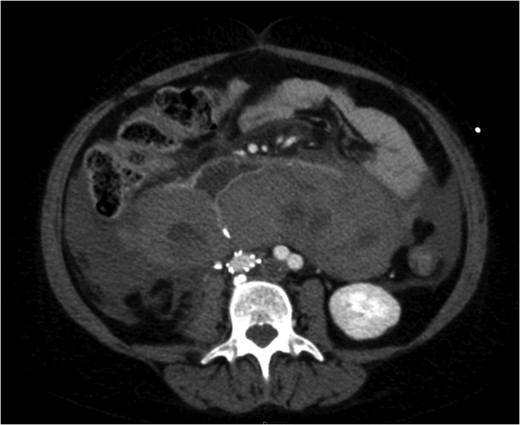

A venous phase abdominal CT demonstrating the end of the IVC filter strut penetrating the wall of the third part of the duodenum.

A coronal section of a venous phase abdominal CT demonstrating the end of the IVC filter strut penetrating the wall of the third part of the duodenum.